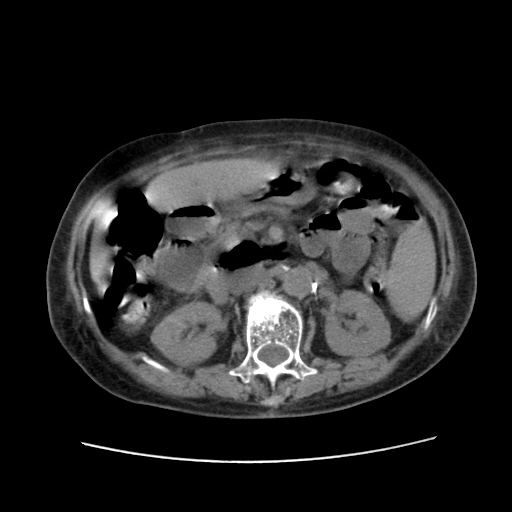

女,77.无不适

肝脏变异、异位胆囊,肝右叶肝内胆管结石并肝内胆管扩张。

肝右叶肝内胆管结石并肝内胆管扩张。

肝右叶肝内胆管结石并肝内胆管扩张

胆总管扩张

肝右叶肝内胆管结石并肝内胆管扩张。另:慢性胆囊炎!胆囊窝积液!

肝右叶肝内胆管结石并肝内胆管扩张。胆总管下段梗阻,考虑壶腹部占位。

右侧肝内胆管局限性扩张,其内密度不均匀,扩张的胆管壁增厚,考虑肝内胆管炎合并结石可能性大

肝右叶肝内胆管结石并肝内胆管扩张。胆总管下段梗阻,考虑壶腹部占位。支持